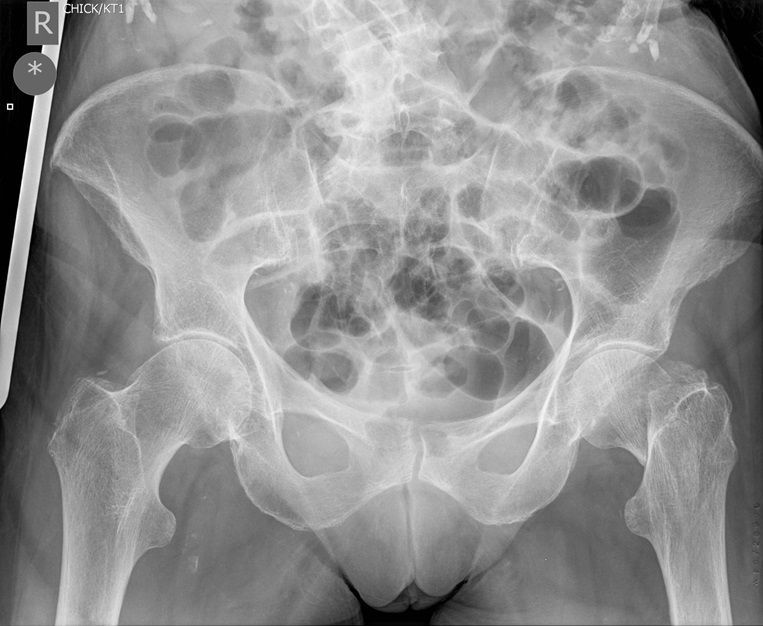

Question 2

Question

Which operation would you perform?

Answer

• THR

• Hemiarthroplasty